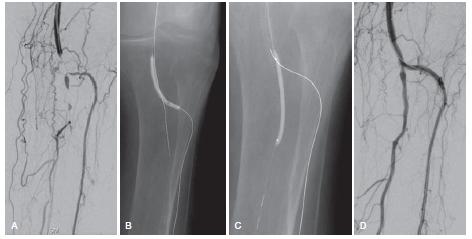

(3)腔内介入治疗,包括单纯球囊成行、支架成行、减容技术以及减容技术联合药物涂层球囊,由于其创伤小,恢复快等优势目前已经成为首选治疗方法。此外血管新生疗法等新型疗法也开始逐渐得到关注。